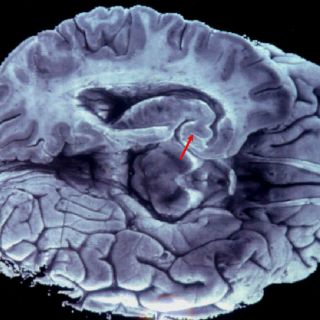

Sin embargo en la actualidad los jóvenes sufren de falta de memoria operativa o memoria "a corto plazo", que es aquella encargada de mantener la información en nuestro cerebro.